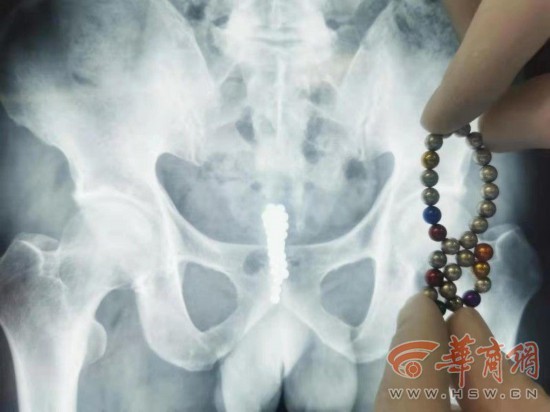

尿道

尿道的相关文章